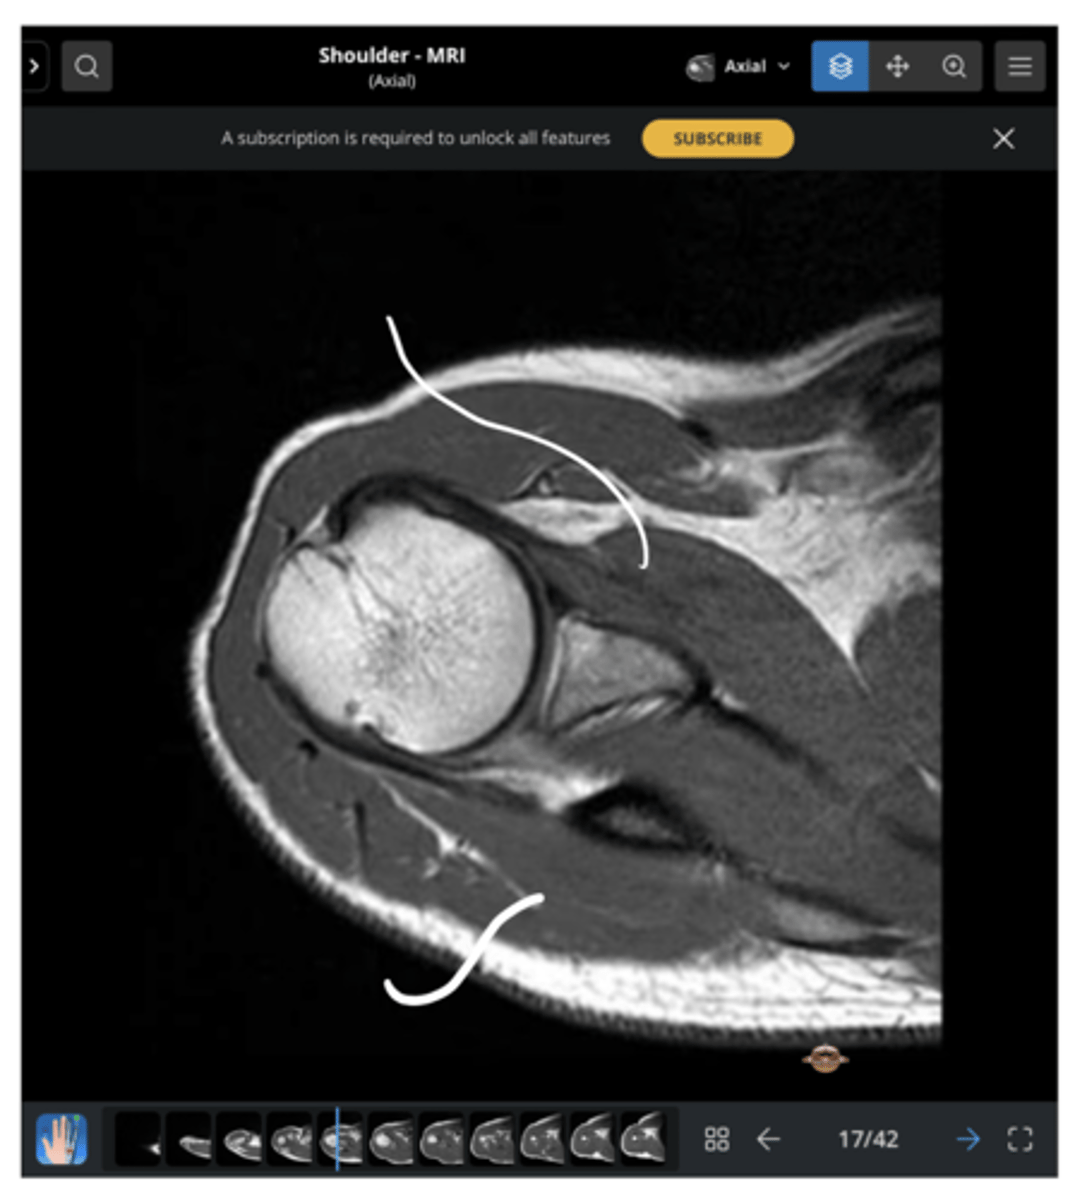

NOTE: this picture is an AXIAL view of the shoulder

AC joint, coracoid, short head of biceps (attaching to the coracoid), long head of biceps (making its way to attach to the superior glenoid labrum), anterior deltoid, and posterior deltoid

Which structures are present in this image as we work our way inwards towards the glenoid fossa and labrum?

Working our way clockwise, which structures are being pointed to in this image?